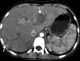

Toxocariasis

Toxocariasis is an illness of humans caused by larvae (immature worms) of either the dog roundworm (Toxocara canis), the cat roundworm (Toxocara cati) or the fox roundworm (Toxocara canis). Toxocariasis is often called visceral larva migrans (VLM). [Source: Wikipedia ]